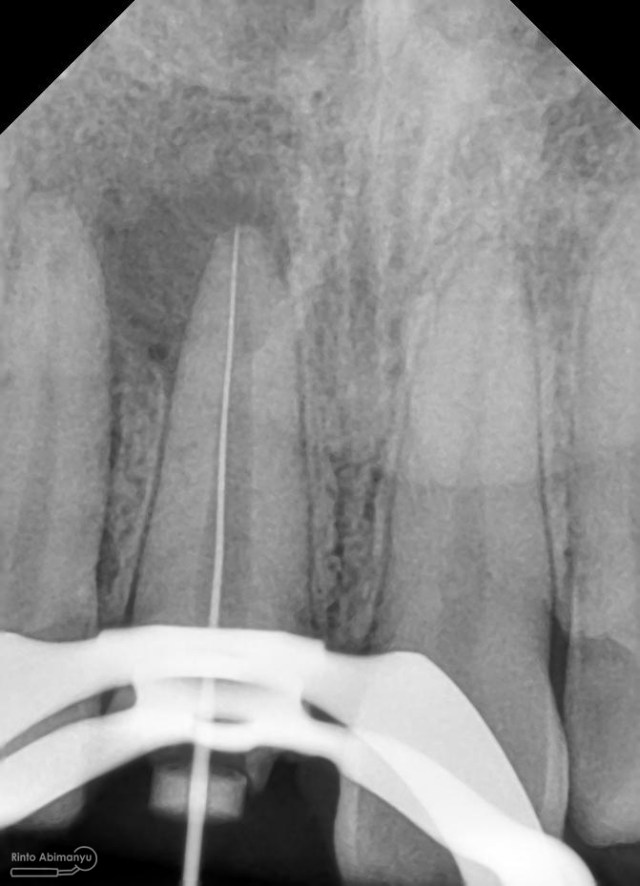

dan ini foto ronsen nya…

Foto radiografis gigi 11 21 22 yang mengalami fraktur

Dari pemeriksaan radiografis lokasi fraktur menyerempet kamar pulpa pada ketiga gigi tersebut… Saya sampaikan kepada pasien bahwa ketiga gigi tersebut memerlukan perawatan saluran akar terlebih dahulu baru kemudian dilanjutkan dengan restorasi indirek… kenapa saya pilih restorasi indirek? Pertimbangannya adalah sisa struktur mahkota gigi yang ada bila hanya di “sambung” dengan restorasi direk dalam jangka panjang rentan mengalami kerusakan, yang kedua pemilihan warna akan lebih maksimal pada kasus ini…. Pasien setuju dengan rencan perawatan yang saya jelaskan…

Kemudian dilakukan pengepasan guttap dan difoto ronsen….

Foto radiografis trial guttap

Dari ronsen terlihat guttap sudah pas dan langsung hari itu juga saya lakukan pengisian saluran akar kemudia pasien pulang…. Pada saat selesai pengisian tidak saya lakukan ronsen lagi karena saya merencanakan ronsen evaluasi pengisiannya sekalian foto ronsen saat pengepasan guttap pada gigi 22 saja biar efektif…

Foto radiografis trial guttap gigi 22

Nah dari foto ronsen ini juga saya melakukan evaluasi hasil pengisian pada gigi 11 21 nya… alhamdulillah pengisian yang kemarin terlihat sepanjang kerja dan padat serta rapat… Pada gigi 22 nya pun pengepasan guttap terlihat sudah sepanjang kerja…

Foto radiografis selesai perawatan saluran akar pada semua gigi

Oo iya tidak lupa juga dilakukan foto ronsen setelah pemasangan crown…

Foto radiografis akhir

Dari foto ronsen terlihat gambaran yang “indah” dari mulai pengisian saluran akar yang rapat dan padat serta gambaran sementasi mahkota yang terlihat homogen….